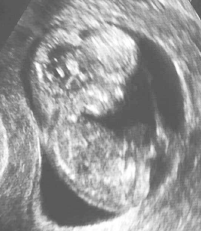

11 week ultrasound

March 23rd